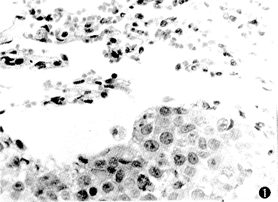

光镜见肺内血管中大量肿瘤细胞组成癌栓,癌细胞同时分布在整个肺泡内,核明显异染,分裂相增多,呈典型的癌转移灶(图1)。

图1 裸鼠的人涎腺腺样囊性癌肺转移灶(HE×400)